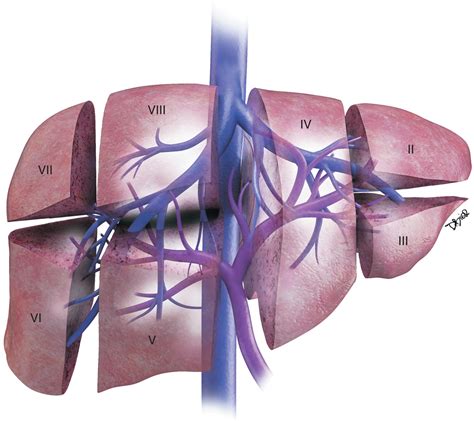

The liver is divided into several lobes, each with distinct functions and anatomical features. The Liver Caudate Lobe is one of these lobes, located in the posterior and superior aspect of the liver. It is situated between the inferior vena cava and the ligamentum venosum. The Liver Caudate Lobe is unique because it receives blood supply from both the hepatic artery and the portal vein, making it a critical component of the liver's vascular system.

The Liver Caudate Lobe is further divided into two segments: the caudate process and the paracaval portion. The caudate process extends to the left and is in close proximity to the ligamentum venosum, while the paracaval portion is adjacent to the inferior vena cava. This anatomical positioning allows the Liver Caudate Lobe to play a significant role in the liver's overall function.